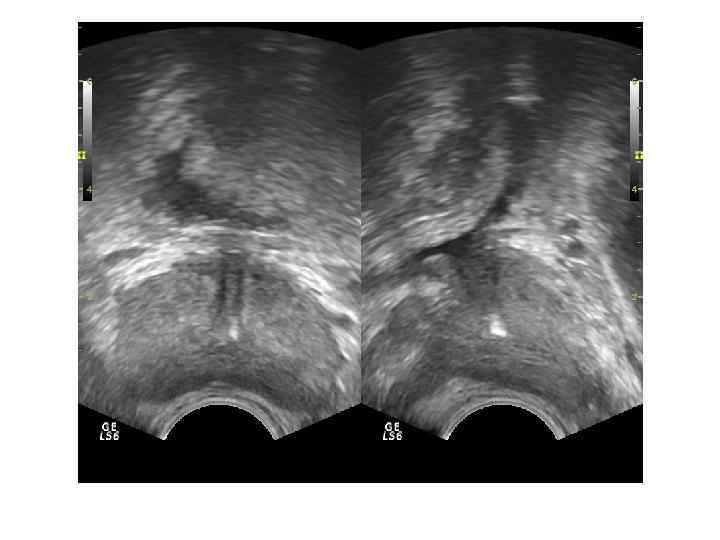

Для трансректального исследования (ТРУЗИ) простаты необходим полостной трансректальный датчик 7, 5— 10, 0 МГц. При ТРУЗИ возможно точное определение размеров и объема железы, выявление тонких структурных изменений и особенностей кровоснабжения паренхимы. Исследование позволяет детально оценить состояние железы при ДГПЖ, особенности роста аденоматозных узлов, состояние паренхимы и капсулы. Трансуретральное исследование простаты не имеет существенных преимуществ перед трансректальным при значительно более инвазивной технологии.

Ультразвуковая картина нормы Необходимо оценить: • • Форму Симметричность Размер Эхогенность Эхоструктуру Контуры Наличие дополнительных объемных образований • Состояние простатической уретры • Состояние парапростатической клетчатки

При ТРУЗИ объем простаты может быть определен с помощью нескольких методов: 1. Объем =А х В х С х 0, 52 (рис. 6. 5 А), где А — продольный размер, В — переднезадний размер, С — поперечный размер. Поперечный размер железы определяется при поперечном сканировании в ее средней части, переднезадний и продольный размеры — при сагиттальном сканировании 2. Объем = С 2 х В х 0, 52 где В — передне-задний размер, С — поперечный размер. 3. Объем = С 3 х 0, 52 где С — поперечный размер.